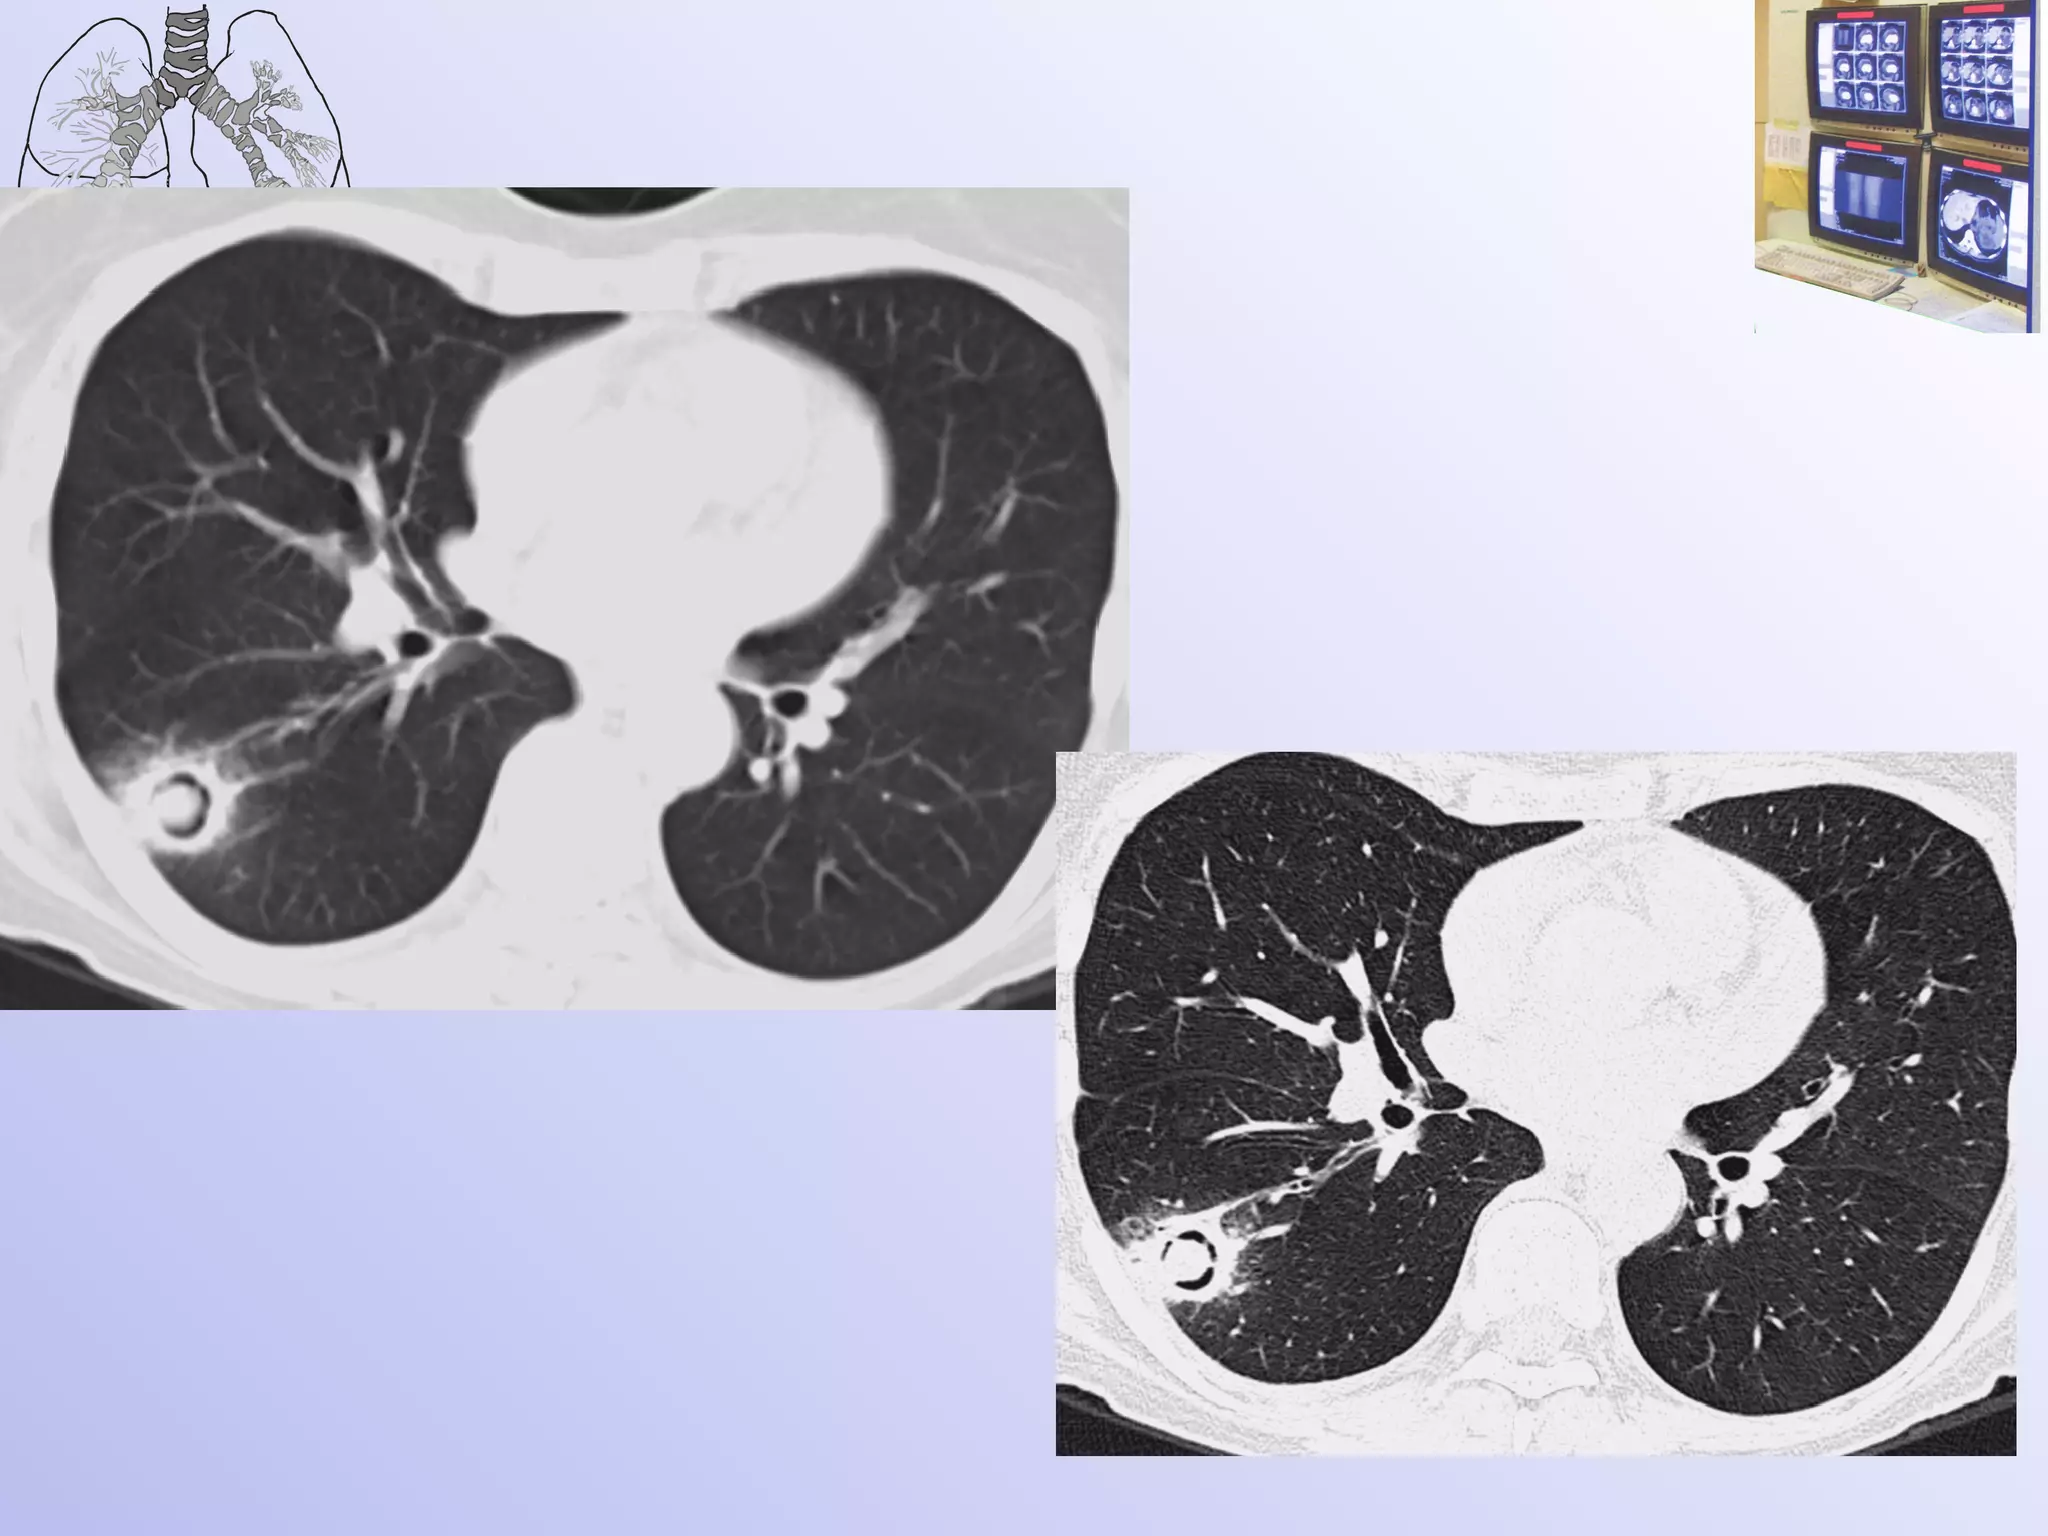

Инвазивный микоз Развитие патологического процесса в легких за 2 дня Киприянова

Трудности в постановке диагноза возникали при появлении множественных полостных образований в легких с тонкими стенками на фоне неизмененной легочной ткани. В отдельных полостях определялись шаровидные массы, что заставило расценить выявленные в легких изменения как проявления аспергиллеза